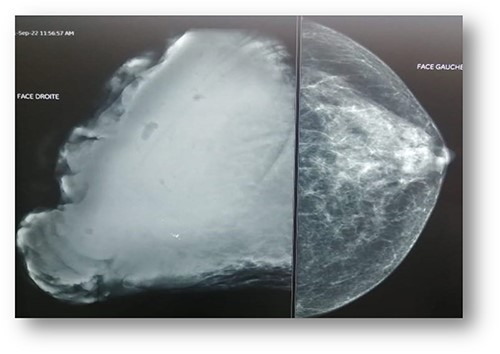

Ultrasonographic examination showed large heterogenous hypoechoic mass vascular on doppler with polylobed contours of 18 × 16 × 10 cm (Fig. 2). Mammography showed an enlarged right breast through the presence of a voluminous opacity with a focus of vermicular microcalcifications (Fig. 3). The lesion was graded BI-RADS score 5 (Breast Imaging-Reporting and Data System score—American College of Radiology).

Mammography: voluminous opacity with a focus of vermicular microcalcifications.